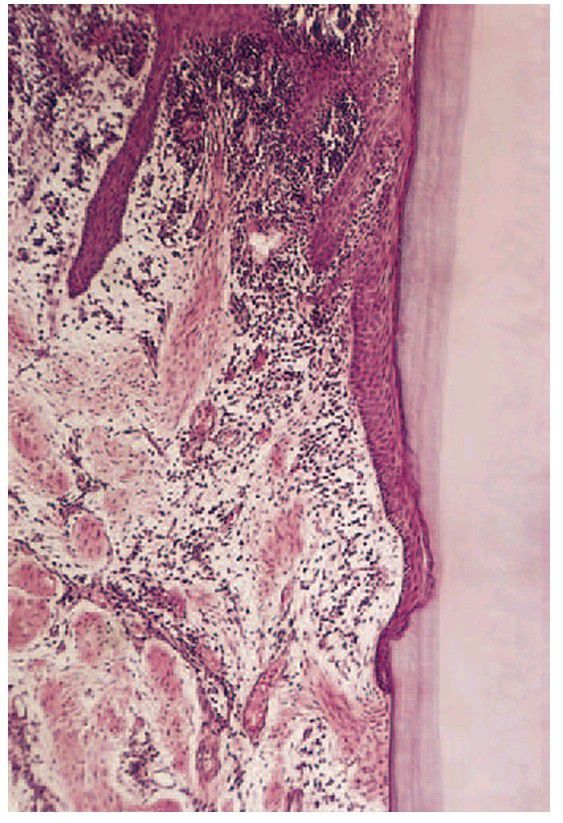

Chronic periodontitis

. Higher-power view showing the epithelial attachment lying against cementum. Note how collagen has been lost from the areas containing infl ammatory cells.